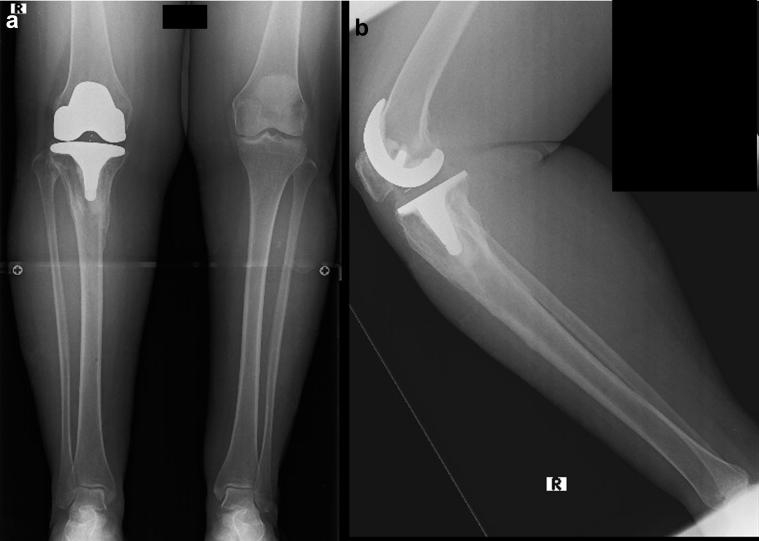

环形六足外固定治疗人工关节周围胫骨骨折

Circular hexapod external fixation for periprosthetic tibial fracture.

A poor soft tissue envelope often accompanies periprosthetic tibia fracture around a well-fixed total knee arthroplasty and the tibial stem leaves little room for screw fixation. This article describes the practicability and effectiveness of a novel surgical technique using circular hexapod external fixation, in patients with this clinical scenario. It was applied for fixation of periprosthetic tibia fracture in 2 patients. Contact between the external fixation pins and the prosthesis was avoided. Using a web-based software program, a gradual reduction in all planes was achieved. Adequate fixation, stability, reduction, and quick healing were obtained in the 2 cases, with minimal complications. The patients returned to their activity level a few months after external fixation removal.

摘要

在固定良好的全膝关节置换周围,假体周围胫骨骨折常伴有软组织覆盖不佳的情况,且胫骨干假体柄几乎没有用于螺钉固定的空间。本文描述了一种使用环形六足外固定的新型手术技术在这种临床情况下的实用性和有效性。该技术应用于2例假体周围胫骨骨折的固定。避免了外固定针与假体之间的接触。通过基于网络的软件程序,在所有平面上实现了逐步复位。2例患者均获得了充分的固定、稳定性、复位及快速愈合,并发症极少。外固定拆除后几个月,患者恢复到了之前的活动水平。